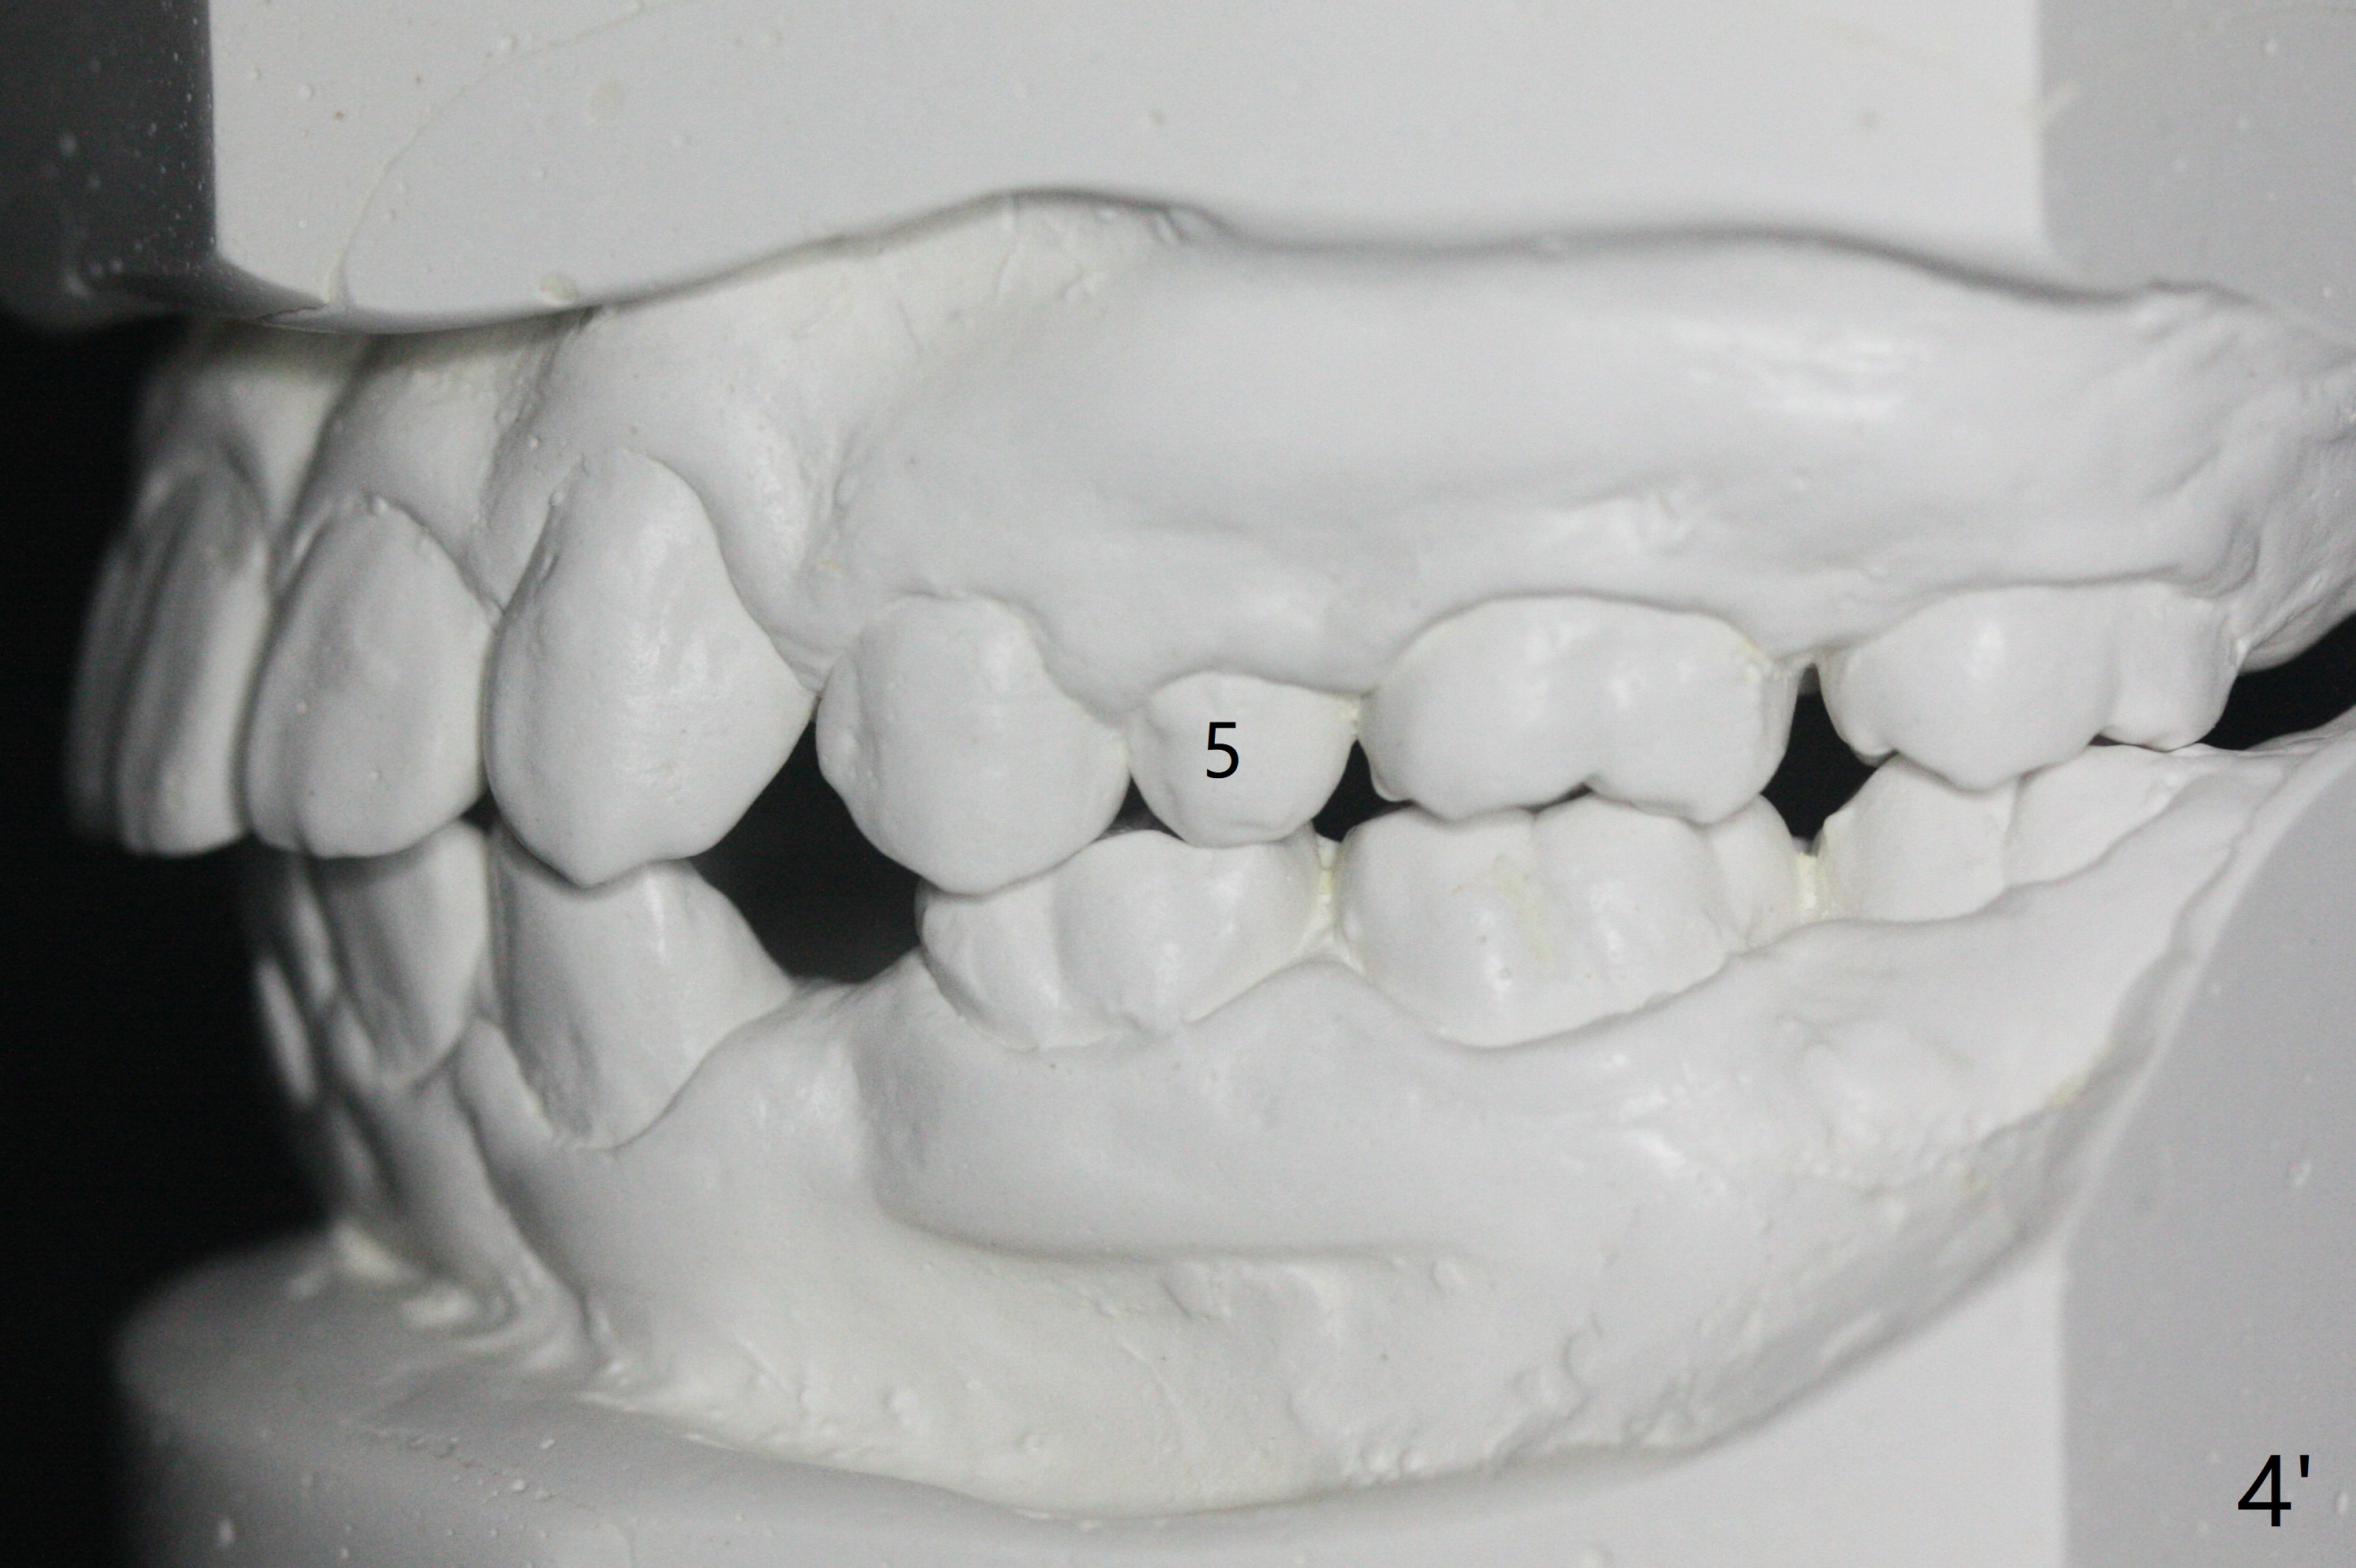

One-year-8-month orthodontic treatment reduces anterior overjet (Fig.1 (double arrows),1', with facial profile improvement), corrects right 1st molar cross bite (Fig.2,2') and dental midlines (Fig.3,3'), closes the diastema between UL3 and 4, extrudes UL5 (Fig.4,5,4',5'), and increases space for future implant at LL4 (Fig.6,6'). In fact large arches with distemata make the treatment possible! Extrusion of UL5 leads to root development (Fig.7, 7' (R)). The increased space at LL4 (Fig.7' *) appears insufficient for an implant.